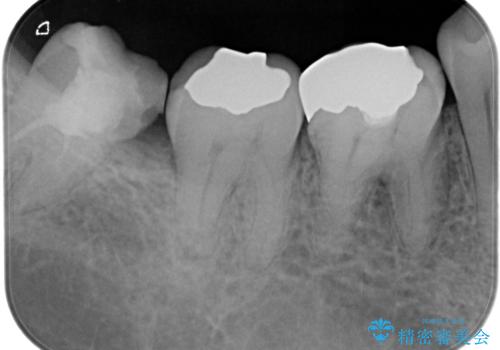

【根管治療】噛んだ時にしみる。最近になってズキズキ痛み、長引く痛みがある

担当医 河口智英